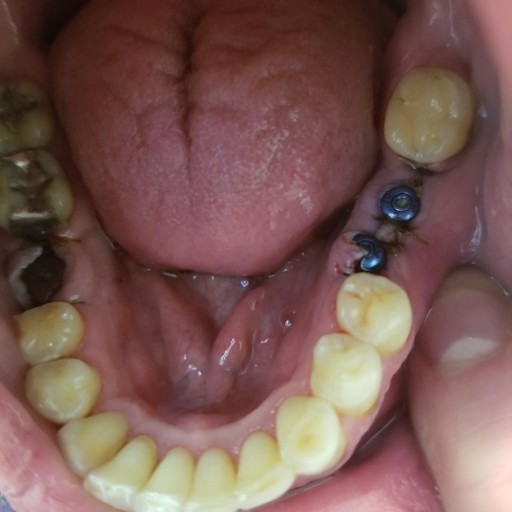

I had 3 implants done yesterday, with 2 that were next to each other (see picture). One is not aligned. I am also doing ortho care and went in today to have a new retainer fitted. The dentist said he did not want to do new impressions due to the...